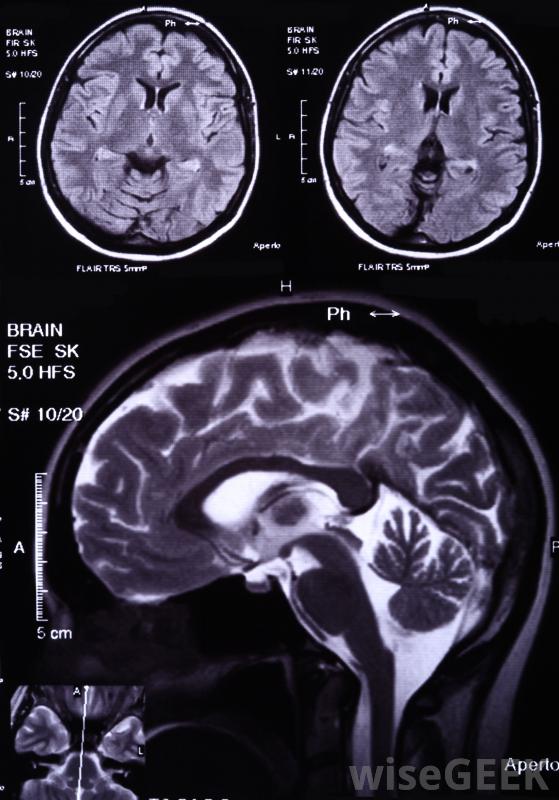

帕金森病、阿尔茨海默病和阿尔茨海默病;多发性硬化症是与白质病变有关的一种特殊的健康状况,它与白质病变有关。大多数情况下,首先注意到额外的症状,导致磁共振成像(MRI)扫描发现病变。它们通常在屏幕上显示为白色或非常浅灰色,尽管其名称实际上来源于浸泡在甲醛中的脑组织的颜色。这种情况的治疗通常包括减缓疾病进展的药物

脑白质病变很可能在MRI扫描中发现。